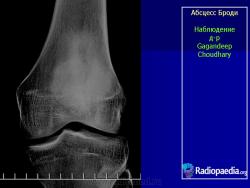

Рентгенологически обнаруживают полость с чёткими склерозированными контурами, при обострении периостальные наслоения, остеосклероз.

Рис. 208. Хронический костный абсцесс Броди в верхнем метафизе большеберцовой кости.

Характерен для абсцесса Броди значительный остеосклероз губчатого вещества, окружающего полость, и лишь очень редко гнойник лежит среди нормальной спонгиозной ткани. На поверхности кости периостальные наслоения очень незначительны, так что если вообще имеется цилиндрическое или, скорее, веретенообразное утолщение метафиза на уровне гнойника, то только в самой умеренной степени. Как правило, секвестрации не бывает. До прорыва наружу или в полость соседнего сустава, несмотря на его близость, дело доходит лишь в редчайших случаях.

Рентгенологическое исследование имеет решающее диагностическое значение. Все детали патологоанатомической картины абсцесса Броди передаются в точности и на рентгеновских снимках (рис. 207 и 208). Изолированная, правильной округлой формы полость, без секвестра, с резко ограниченными гладкими внутренними контурами, расположенная среди склерозированного губчатого вещества, на типичном месте — в метафизарном конце большой трубчатой кости, слегка утолщенной благодаря периостальным наслоениям, — эта рентгенологическая картина при поддержке клинических симптомов разрешает диагностическую задачу. При этом следует учесть, что между, так сказать, классическим типичным абсцессом Броди и другими формами хронического остеомиелита бывают и переходные формы — и по местоположению, размерам, форме, характеру реактивных изменений в окружности, секвестрации и т. д. Это ведь в природе вещей: классификация показывает всегда несколько условно типичное, жизнь преподносит многообразие, не укладывающееся в строгую жесткую схему. Никоим образом не следует злоупотреблять диагнозом абсцесса Броди и ставить его расширительно, чуть ли не во всех случаях более или менее ясно выраженной полости при обычном хроническом остеомиелите: абсцесс Броди — это совершенно определенное клинико-рентгено-анатомическое понятие, это четкая нозологическая единица, и диагноз оправдан лишь в тех случаях, когда рентгенологическая картина удовлетворяет всем вышеперечисленным критериям.